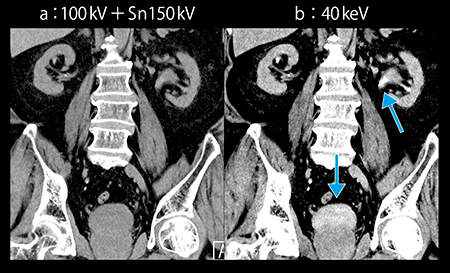

また,腎部分切除術では,腎杯損傷防止のためCT Urography(CTU:排泄相)にて腎杯と腫瘍との距離を確認する必要があるが,排泄相では腎実質の造影の低下により,腫瘍のコントラストが不十分となる。Dual Energy ImagingのMono+は,従来よりもSNRに優れた仮想単色X線画像を作成可能である。120kV相当の画像である100kV+Sn150kV画像では不明瞭な病変も,Mono+の40keV画像ではコントラストが明瞭となる(図2)。

図2 Mono+の40keV画像(c)による腎腫瘍の描出

続いて撮影した腎実質相および排泄相では造影剤量が不十分であるが, Mono+の40keV画像により,ノイズが増加することなく腎実質の造影効果が増強し,腫瘍と腎実質のコントラストが確認できた(図6)。また,わずかに尿路に排泄された造影剤と腫瘤とのコントラストも得ることができた(図7 b↓)。

図7 症例2:Mono+の40keV画像による造影剤20mLでの排泄相の描出